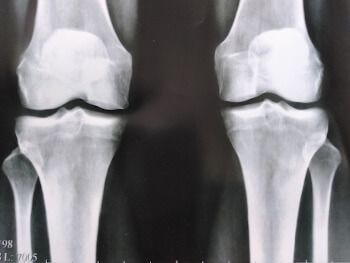

El efecto de la artrosis en el cartílago de la articulación de la rodilla.

Por desgracia, el médico tenía razón... Al cabo de dos meses, me resultaba insoportablemente doloroso estar de pie, las medicinas y los analgésicos dejaron de hacerme efecto, aunque me había gastado mucho dinero en ellos, y las medicinas me perjudicaban mucho el estómago y el hígado: ¡tuve que renunciar a ellas! Tuve que comprar una silla de ruedas y usarla para moverme por el apartamento... El médico me dijo que la artritis destruye el cartílago en 3 años, pero debió empezar mucho antes, lo interesante es que no sentía que mis articulaciones estuvieran mal, pero luego, todo empeoró de repente y me vi sentada en una silla de ruedas, sin ninguna esperanza de recuperación, recuerdo que las lagrimas corrieron por mis ojos, fue el peor momento de mi vida......